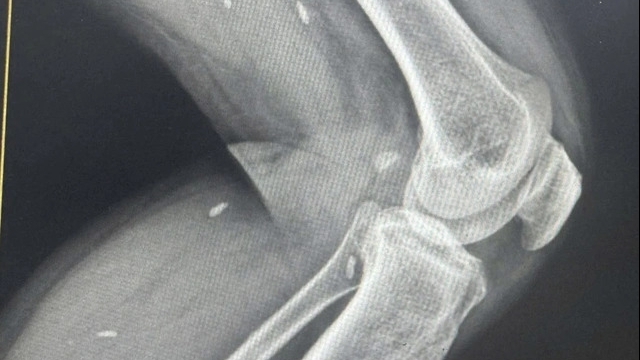

Một nam giới bị biến chứng cắt bao quy đầu sau khi phẫu thuật ở phòng khám tư